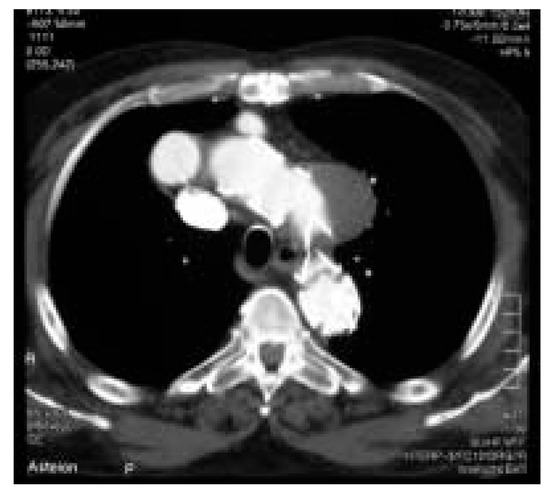

Une patiente de 31 ans souffrant d’une cardiopathie congénitale consulte car elle souhaite une grossesse [...]